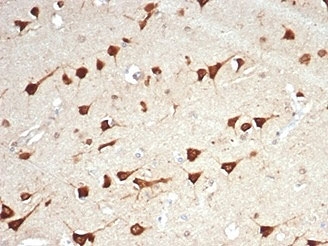

IHC staining of FFPE human brain tissue with LPLUNC1 antibody (clone LPLUNC1/7059R). HIER: boil tissue sections in pH 9 10mM Tris with 1mM EDTA for 20 min and allow to cool before testing.